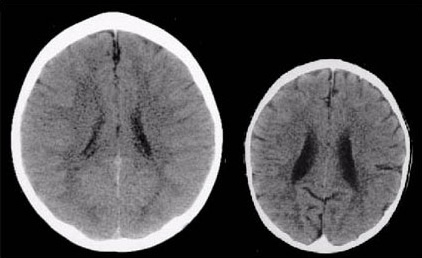

Research from the National Scientific Council on the Developing Child (2012) and Perry and Pollard (1997) has reported on the effects of sensory stimulation, or the lack of it, on early brain development. Using data from CT scans, physical measurements and documentary sources they explored the brain development of a group of neglected children. As an example of what can happen in an extreme case of sensory deprivation, Perry and Pollard published the startling images shown below.

These images illustrate the negative impact of neglect on the developing brain. The CT scan on the left is from a healthy three-year-old child with an average head size (50th percentile). The image on the right is from a three-year-old child following severe sensory-deprivation neglect in early childhood. This child's brain is significantly smaller than average and has abnormal development of the cortex (cortical atrophy) and other abnormalities suggesting under-development and mal-development of the brain. The contrast is marked but it is important to remember the comparison is with a very extreme example.